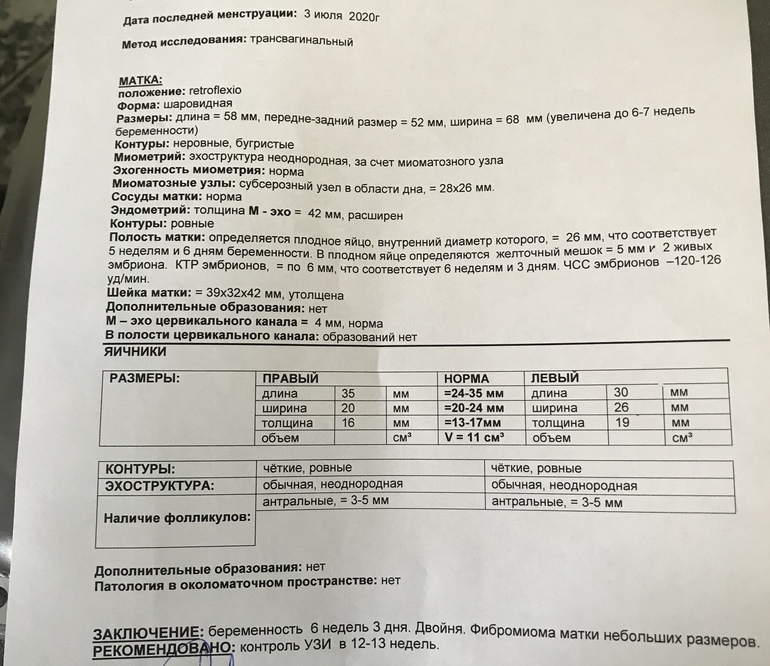

Внутриутробное развитие двойни/тройниЭКО Беременность (6,4 по месячным). Подсаживали 2 эмбриона, но на втором узи на 28 дпп обнаружили два эмбриона в одном пя. То есть один прижился и поделился!! И при этом ОДИН жм!!! Это норм? Посмотрите, пожалуйста узи!!! Беременность первая. Я очень боюсь!